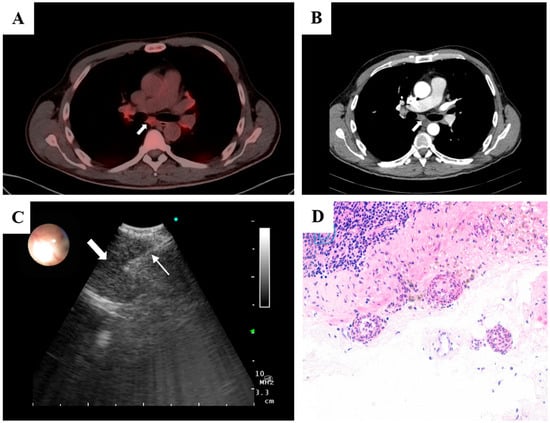

PET–CT showed hypermetabolic bilateral hilar and mediastinal lymphadenopathy (SUVmax 4.0–5.0) with incipient bilateral basilar pulmonary fibrosis. There was no evidence of malignancy or large-vessel vasculitis. Given the PET–CT pattern without an identifiable primary, negative blood and nodal cultures with a normal echocardiogram, and lack of response to appropriate antibiotics, infectious and malignant etiologies were deprioritized. Because architecture-preserving tissue was needed to assess vessel-wall injury and exclude granulomatous disease, we selected EBUS-TMC to obtain an intact core from the small subcarinal node. Histology demonstrated neutrophilic small-vessel vasculitis with fibrinoid necrosis; together with high-titer MPO-ANCA and clinical improvement only after immunosuppression, these findings supported MPA. EBUS (BF-UC180F, Olympus, Tokyo, Japan) identified a 9 mm subcarinal lymph node (maximum standardized uptake value 4.6). A transbronchial needle aspiration was performed using a 22G EBUS-TBNA needle (SonoTip® TopGain, Medi-Globe) and the Ariza-Pallarés tunneling method, followed by an EBUS-TMC of the node with a 1.1-mm cryoprobe (Erbecryo 20402-401, Tübingen, Germany), obtaining high-quality samples without complications (Figure 1). Histopathological examination confirmed neutrophilic small-vessel vasculitis with fibrinoid necrosis, consistent with microscopic polyangiitis. No granulomas or malignant cells were observed. Microbiological cultures of the sample showed no growth.

Figure 1.

(A) PET–CT showing bilateral hypermetabolic hilar and mediastinal lymphadenopathy (SUV_max 4.0–5.0), including a 9 mm subcarinal node (SUV_max 4.6); no FDG-avid primary tumor or large-vessel uptake. (B) Axial contrast-enhanced CT depicting the subcarinal lymph node corresponding to the PET-avid focus. (C) Linear EBUS view after the tunneling approach showing the 1.1 mm cryoprobe (thin arrow) within the target subcarinal node (thick arrow), with real-time Doppler used to confirm an avascular trajectory. (D) High-power photomicrograph (H&E) of the nodal capsule demonstrating small-vessel vasculitis with leukocytoclasia, segmental vessel-wall destruction, and fibrinoid necrosis, with preserved nodal architecture and no granulomas or malignancy.